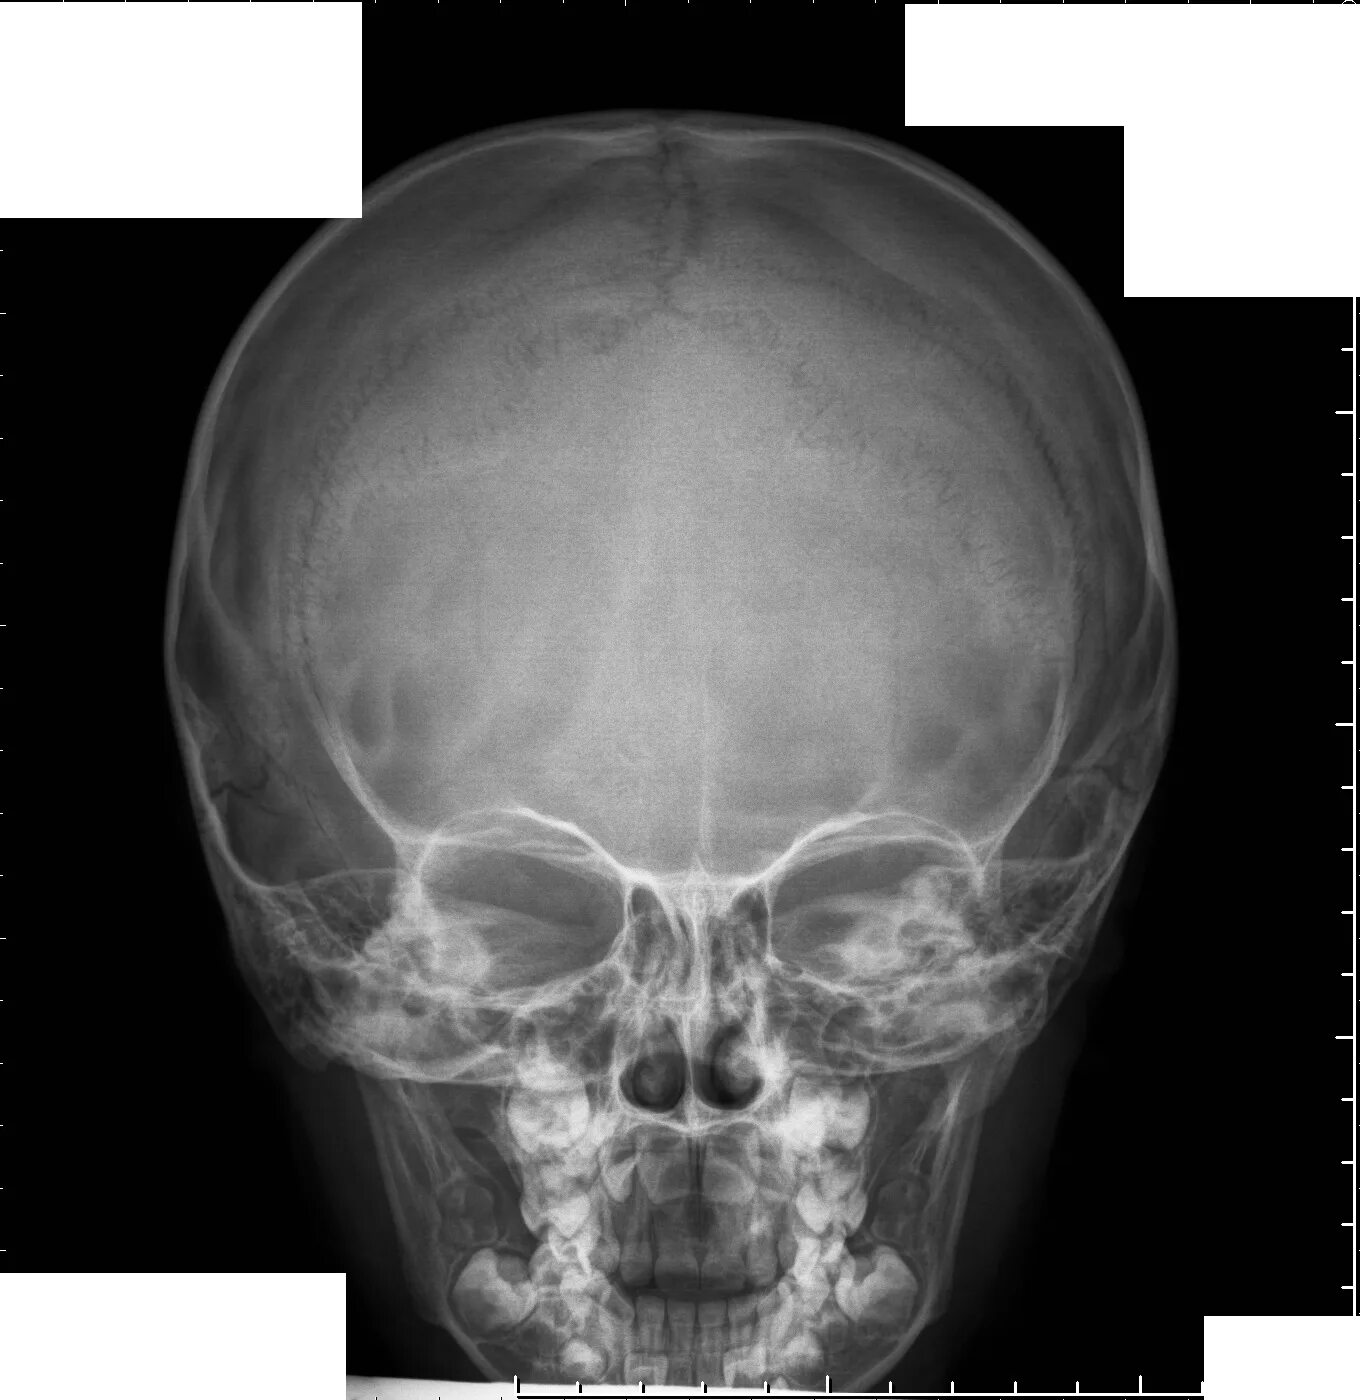

Проекции рентгенограмм черепа